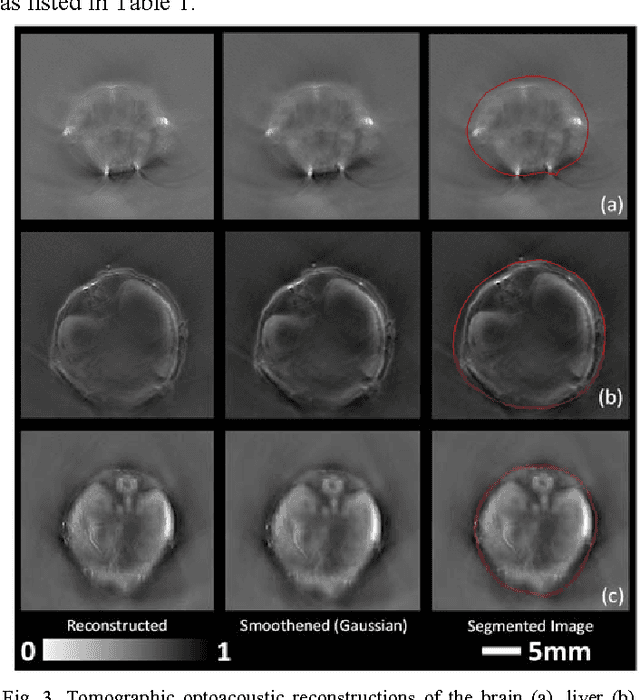

Abstract:Segmentation of biomedical images is essential for studying and characterizing anatomical structures, detection and evaluation of pathological tissues. Segmentation has been further shown to enhance the reconstruction performance in many tomographic imaging modalities by accounting for heterogeneities of the excitation field and tissue properties in the imaged region. This is particularly relevant in optoacoustic tomography, where discontinuities in the optical and acoustic tissue properties, if not properly accounted for, may result in deterioration of the imaging performance. Efficient segmentation of optoacoustic images is often hampered by the relatively low intrinsic contrast of large anatomical structures, which is further impaired by the limited angular coverage of some commonly employed tomographic imaging configurations. Herein, we analyze the performance of active contour models for boundary segmentation in cross-sectional optoacoustic tomography. The segmented mask is employed to construct a two compartment model for the acoustic and optical parameters of the imaged tissues, which is subsequently used to improve accuracy of the image reconstruction routines. The performance of the suggested segmentation and modeling approach are showcased in tissue-mimicking phantoms and small animal imaging experiments.